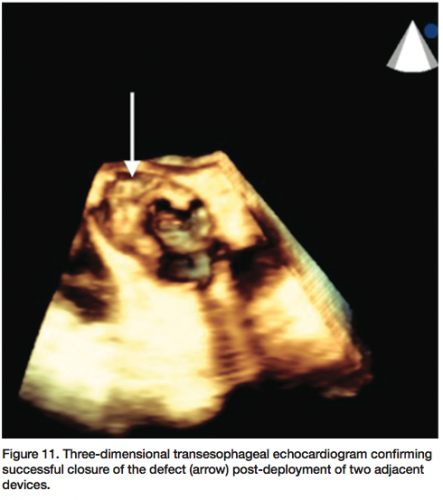

The patient underwent general anesthesia and endotracheal intubation for TEE evaluation in the cardiac catheterization laboratory. The paravalvular leak was crossed using a 6 French multipurpose diagnostic catheter and angled Glidewire, followed by a 6 French shuttle sheath (Cook Medical) over an Amplatz stiff wire (Figure 7). Using TEE and fluoroscopy, an 8 mm Amplatzer vascular plug II (AGA Medical) was deployed successfully, with persistent moderate regurgitation from the anteromedial region of the paravalvular aortic leak (Figure 8). The defect was

recrossed with a 5 French EBU guide catheter (Medtronic), followed by placement of a second 8 mm Amplatzer vascular plug (Figure 9). Final angiography (Figure 10) and TEE (Figure 11) of the paravalvular leak after two adjacent vascular plugs demonstrated no significant residual paravalvular leak. All catheters and sheaths were removed, with hemostasis achieved using a vascular closure device. The patient was discharged home without complications the following day.